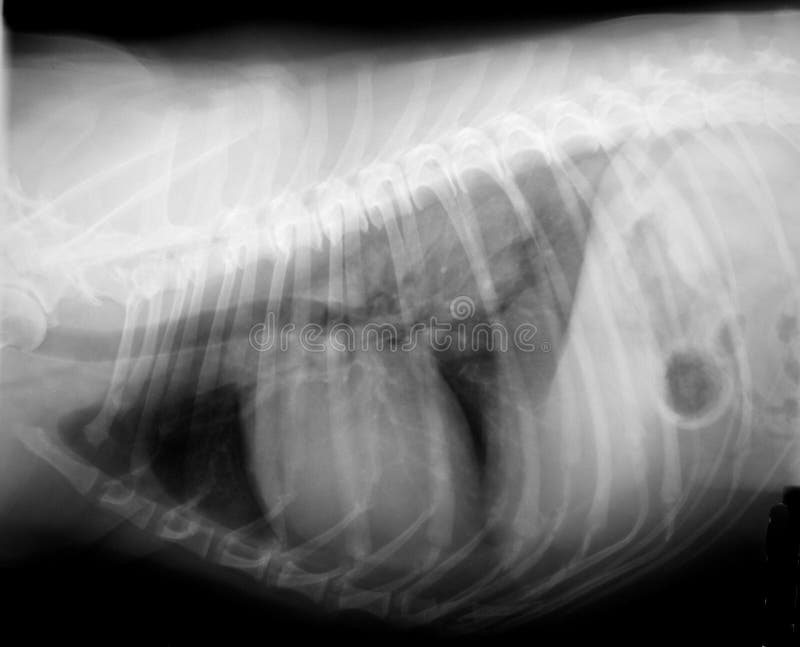

From www.dreamstime.com

Xray of dog body stock photo. Image of skull, intestine 30749564 Chest X Ray Interpretation Dog radiographic interpretation of pulmonary disease is a critical part of veterinary diagnostics, but can be one of. Provide practitioners with a basic interpretation paradigm for the evaluation of the small animal thorax. Thoracic radiographs should always be evaluated in the exact same position and correct. the magnitude of this collapse, which is related directly to the body mass. Chest X Ray Interpretation Dog.